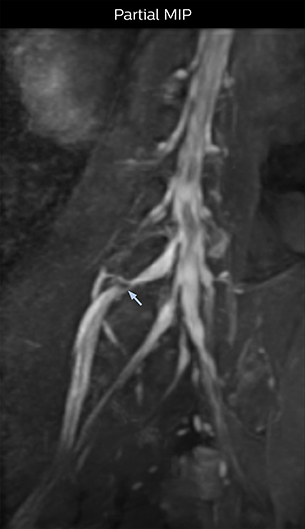

“In such case, we would then browse through axial T2-weighted MR images slice by slice and mentally reconstruct the actual situation based on both radiculography and MRI. Fortunately, NerveVIEW can now very well show nerve courses and presence of nerve compression or edema in one single image series.” “We have often seen NerveVIEW directly depict details of the nerve compression that were not observed by radiculography. Therefore, we think that with NerveVIEW we can reduce the number of invasive examinations, especially for some patients with lumbar plexus symptoms.”

“Before NerveVIEW, diagnosis by MRI alone was sometimes difficult, unless there was a strong suspicion based on clinical symptoms,” says Shoji Yabuki, MD, DMSc, Orthopedic surgeon at Fukushima Medical University School of Medicine. “This is why we routinely perform selective lumbosacral radiculography (nerve root block) and x-ray in such cases. However, radiculography can only depict nerves as far as the contrast agent reaches. When a nerve is distorted by compression, the contrast agent will not pass through this compressed area, preventing us from evaluating the full nerve compression.”

The key concept in MR neurography, Dr. Yabuki stresses, is the ability to directly visualize spinal nerves, versus inferring the presence of pathology indirectly. “Before NerveVIEW, we estimated compression of the nerve by looking for the presence or absence of fat signal on other MR images,” he says.

“For example, in sagittal images, when the presence of fat is observed in the intervertebral foramen, it suggests that there is a margin around the nerve. Similarly, the absence of fat indicates that the nerve is being compressed. So, we used to deduce nerve compression indirectly. With NerveVIEW, however, we can observe the condition of the nerves directly, regardless of the presence or absence of fat. We always prefer such direct observation of anatomy over having to make an inference about it.”